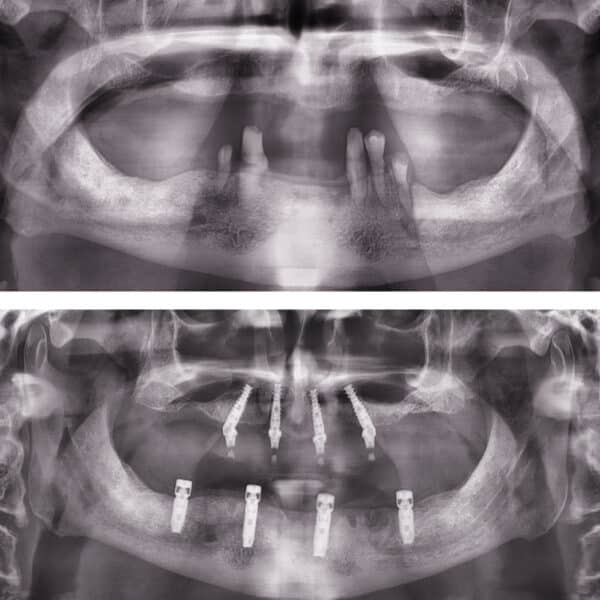

Implantul dentar este adesea recomandat deoarece prezintă foarte multe avantaje, iar, de multe ori, este unica soluție pentru protezarea unei edentații.